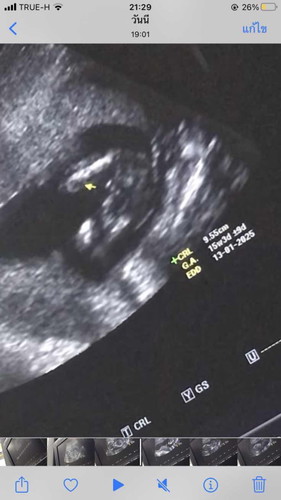

แบบนี้ชายหรือหญิงคะ

สอบถามแม่แม่ค่ะเห็นเป็นยังไงบ้างคะ

ชายค่ะ ถ้าหญิงจะแบบของเรา

น่าจะชายนะคะ